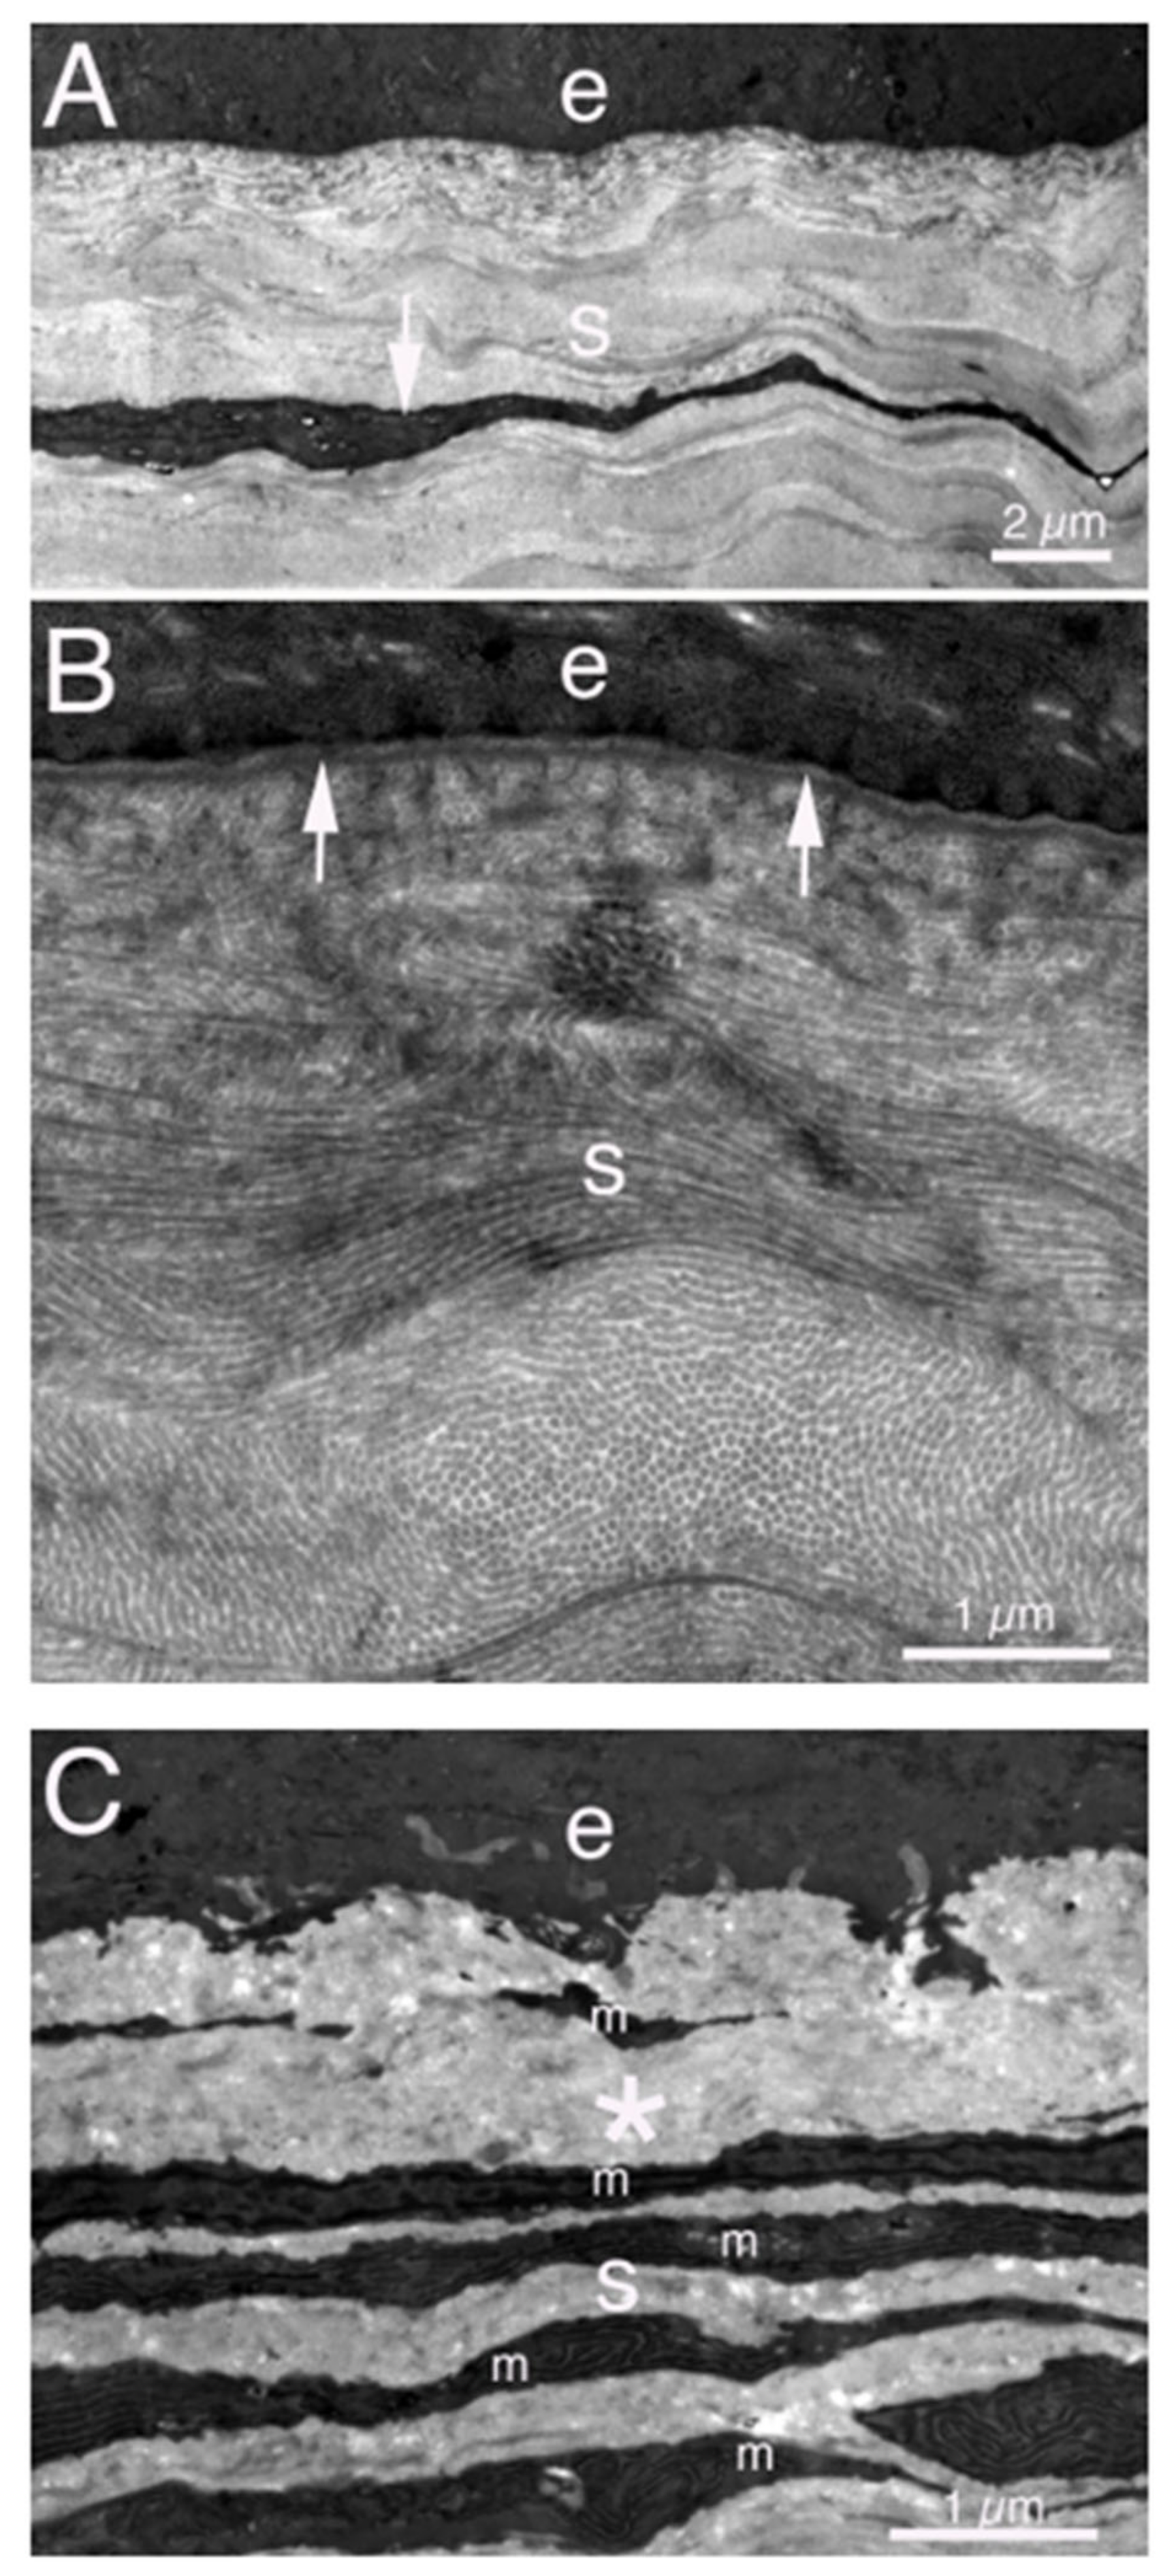

- Torricelli, A.A.M.; Singh, V.; Agrawal, V.; Santhiago, M.R.; Wilson, S.E. Transmission electron microscopy analysis of epithelial basement membrane repair in rabbit corneas with haze. Investig. Ophthalmol. Vis. Sci. 2013, 54, 4026–4033. [Google Scholar] [CrossRef] [PubMed]